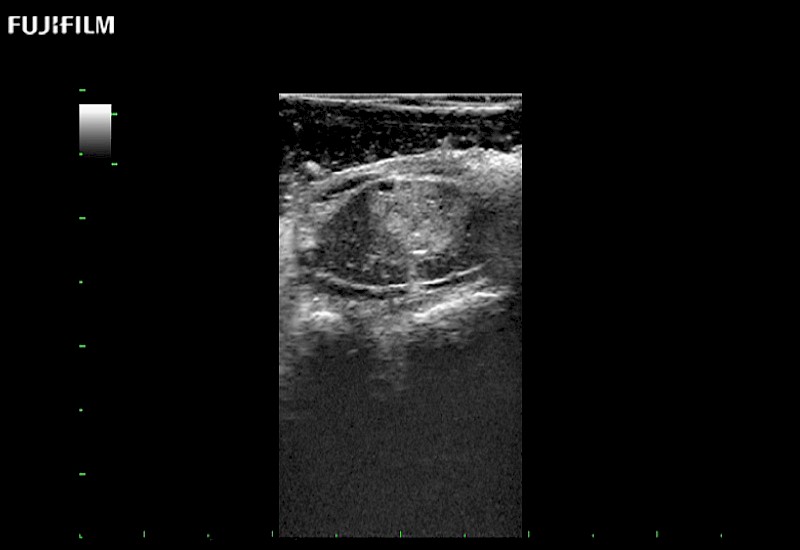

The world's only phased array burr-hole transducer that is ideal for scanning during burr-hole guidance procedures.

Main Specifications: